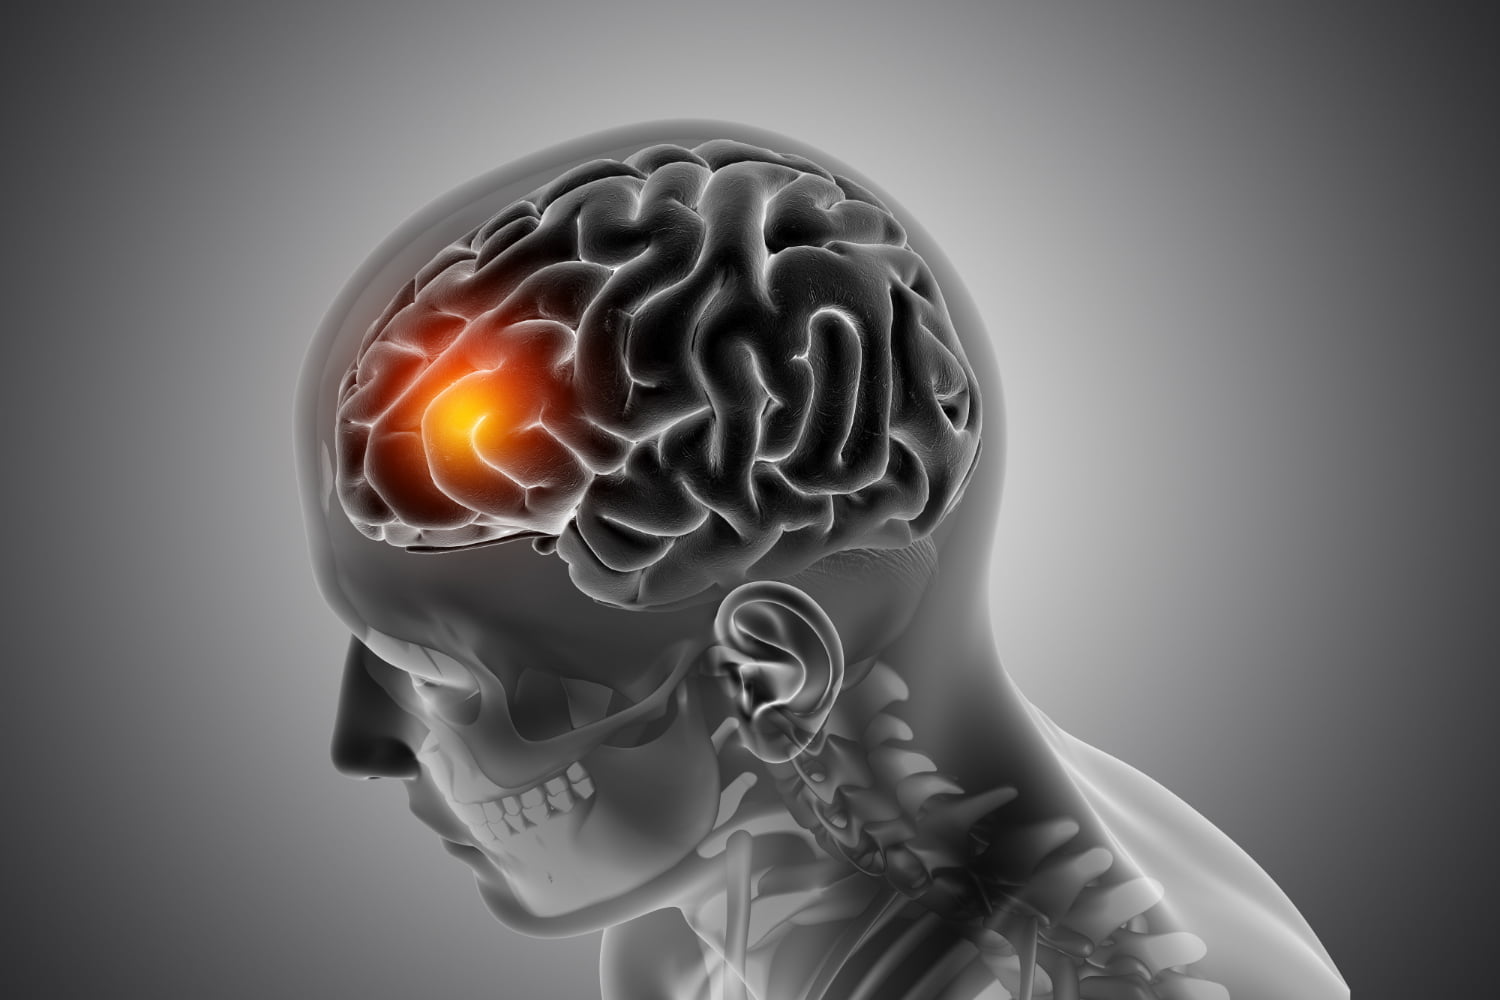

Síntomas de advertencia de un derrame cerebral

Un accidente cerebrovascular, también conocido como ictus, es una afección grave que afecta el flujo sanguíneo al cerebro. Es crucial comprender los síntomas del ictus para poder reconocer los signos de alarma y buscar atención médica de inmediato. El ictus puede ocurrir repentinamente y sin previo aviso, por lo que estar informado es fundamental para tomar medidas rápidas y efectivas.

👉 Seguir canal en WhatsAppEl ictus se produce cuando un vaso sanguíneo que suministra sangre al cerebro se bloquea o se rompe, lo que interrumpe el flujo sanguíneo y priva al cerebro de oxígeno y nutrientes. Esto puede provocar daño cerebral permanente e incluso la muerte si no se trata a tiempo. Por lo tanto, es esencial conocer los síntomas del ictus y actuar de inmediato si se presentan.